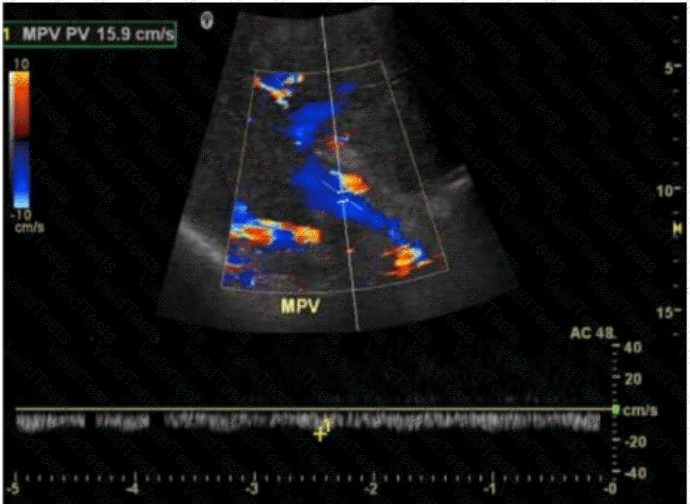

The image shows a color Doppler ultrasound of the main portal vein (MPV), which appears irregular and replaced by multiple small, serpiginous vascular channels — a hallmark of cavernous transformation. Cavernous transformation of the portal vein is a late complication of chronic portal vein thrombosis, in which collateral vessels develop around the thrombosed portal vein to bypass the obstruction.

Key Doppler ultrasound features of cavernous transformation:

Absence of a normal portal vein

Multiple tortuous vessels in the porta hepatis

Color Doppler shows hepatopetal flow in these channels

Low velocity, continuous waveform flow in collateral vessels